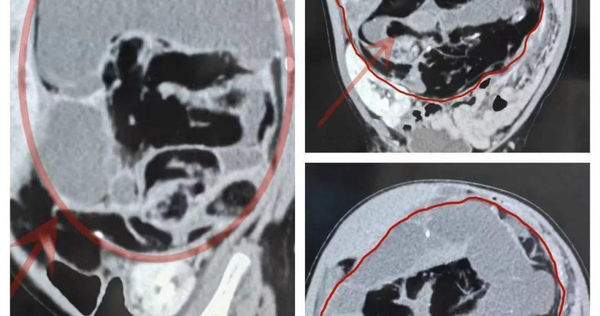

▲女嬰腹腔內器官全錯位。(圖/翻攝自微博)

小寶寶才8個月大,肚子裡竟長了個5斤多重的大腫瘤!從做手術開始,寶寶經歷的一切簡直不敢想像,可謂九死一生。大陸福建省廈門市8個月大的女嬰妙妙(化名)體重16斤(等於台灣的8公斤),腹中藏著一個重達5斤多(約等於台灣2.5公斤多)的腫瘤,霸占了整個腹腔的80%,使得腹腔內所有器官全部錯位。

經過仔細體檢,黃聖余懷疑妙妙的腹腔內長著一個巨大的腫瘤。為了確診,術前妙妙接受了腹部彩超檢查。結果顯示腫瘤約一個胎頭大小,占據了整個腹腔的4/5空間。醫院幫妙妙制定了完善的手術方案,配備經驗豐富、業務精幹的團隊帶著妙妙一路闖關。